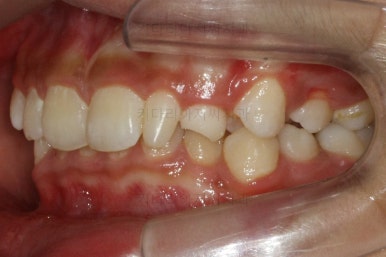

작은 앞니가 왜소치이다 보니 윗니에는 틈이 남아있고 교합도 조금 엉성한 모습이에요.

왜소치의 사이즈가 위아래 교합을 맞춰주는데 방해가 된다고 판단하여 왜소치를 크게 해주기로 결정했습니다.

우선 현재 상태에서는 사이즈를 크게 하지 못하기 때문에 왜소치 좌우로 틈새를 만들어주기로 했습니다.

왜소치 좌우로 틈을 일부러 만든 상태입니다.

치아는 매우 가지런해졌고 뾰족하던 앞니의 형태도 좋아졌어요.

매복되어 있던 송곳니도 잘 나왔고 과개교합도 물론 개선이 되었습니다.

부산교정치과 키다리아저씨치과에서 치료한 이번 치료의 전후사진을 비교해 볼게요.

왼쪽이 치료 전, 오른쪽이 치료 후 모습입니다.